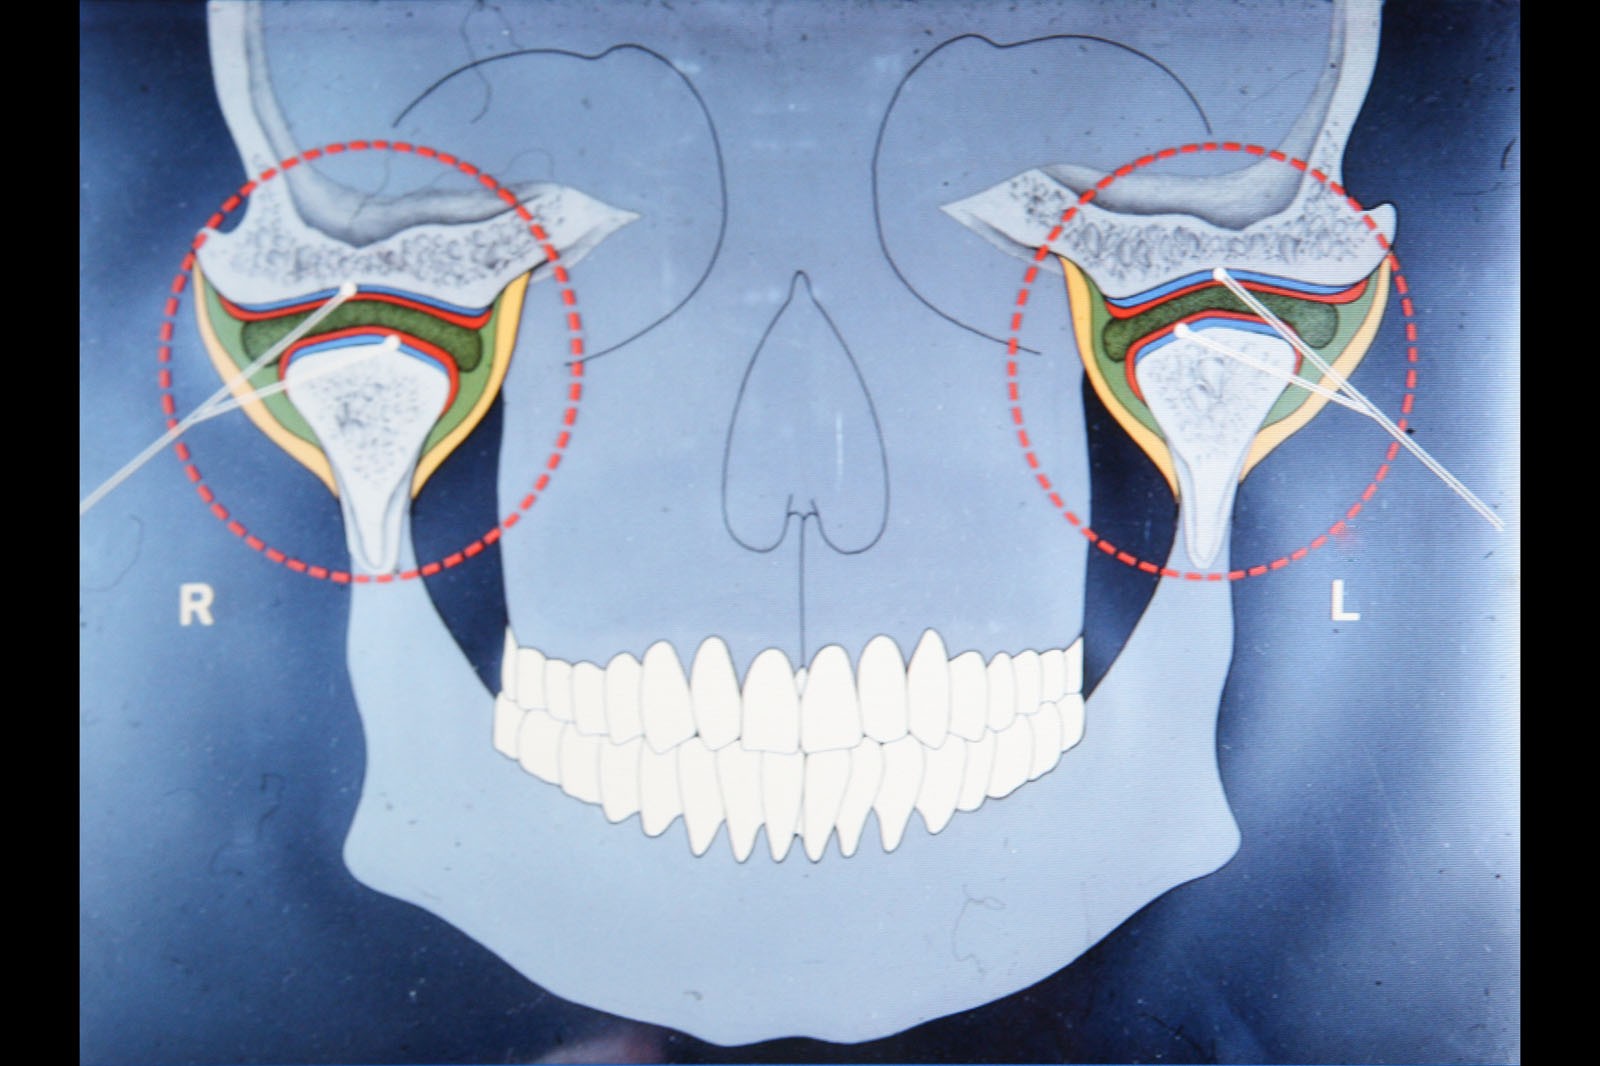

Metoda Gerbera jako punkt wyjścia dla analizy traktuje staw skroniowo-żuchwowy. W relacji do jego funkcji bierze pod uwagę pozostałe ogniwa układu stomatognatycznego. Staw skroniowo-żuchwowy jest działającym synchronicznie symetrycznym elementem anatomii twarzoczaszki, który pozwala na otwieranie ust i funkcje z tym związane. To staw o złożonej budowie, w jego skład wchodzą: dołek stawowy kości skroniowej, który stanowi panewkę stawową, wyrostek kłykciowy, krążek stawowy i torebka stawowa. Krążek zbudowany jest z chrząstki i dzieli jamę stawową na dwie części: górną i dolną. Podczas ruchów opuszczania żuchwy (otwierania ust) krążek stawowy przesuwa się do przodu i dołu. Wraz z krążkiem przesuwa się wyrostek kłykciowy głowy żuchwy po obu stronach. W ruchu przywodzenia żuchwy (zamykania ust) krążek stawowy i wyrostek kłykciowy żuchwy wracają na swoje miejsce do pozycji wyjściowej. Stawy są sprzężone ze sobą czynnościowo (ruch następuje równocześnie w obu stawach) i anatomicznie (łączy je trzon kości żuchwy), stąd też nieprawidłowe asymetryczne obciążenia stawów są najczęstszą z przyczyn zaburzeń narządu żucia.

W ocenie wewnątrzstawowych patologii pomocna jest diagnostyka obrazowa. Konwencjonalne zdjęcia radiologiczne OPG, tomografia komputerowa oraz stożkowa tomografia komputerowa CBCT pozwalają na ocenę elementów kostnych stawu skroniowo-żuchwowego. Ocenę tkanek miękkich zlokalizowanych wewnątrzstawowo umożliwia rezonans magnetyczny NMR.

W celu ustalenia wzajemnej relacji żuchwy i szczęki Gerber poleca rejestrację z użyciem centralnego sztyftu podpierającego, który zapewnia równomierne obciążenie podłoża protetycznego i stawów skroniowo-żuchwowych, a także ułatwia centralne ułożenie głów stawowych dzięki trójpunktowemu podparciu żuchwy w stosunku do czaszki.

W pierwszym etapie wykonuje się modele robocze, które są montowane w opracowanym przez prof. Gerbera artykulatorze. Tak zwany condylator pozwala na symulację trójwymiarowych ruchów głów żuchwy. Pozwala na zweryfikowanie poprawności relacji pomiędzy łukiem zębowym górnym a dolnym. Po dokładnym zbadaniu funkcji i morfologii stawu sż, wykonaniu pomiarów oraz ocenie stanu zdrowia zębów zostaje opracowany indywidualny plan leczenia zgodny z uwarunkowaniami pacjenta.

Dzięki zastosowaniu łuku twarzowego możliwy jest pomiar kątów nachylenia torów przesuwania głów żuchwy. Pozwala to na zamontowanie modeli gipsowych w stosunku do stawów skroniowo-żuchwowych i płaszczyzny Campera (linii uszno-nosowej) orientacyjnej w widoku z profilu. Ma to na celu odtworzenie prawidłowej okluzji, czyli odpowiedniej pozycji stykania się zębów górnych z dolnymi.